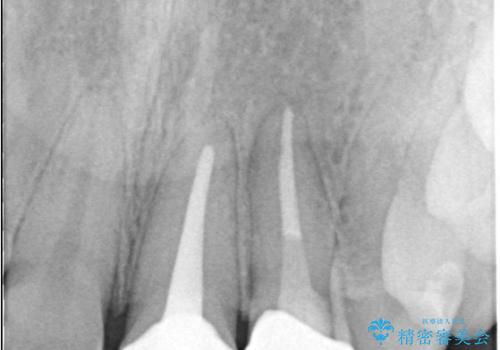

治療結果:

痛みは消失し、患者様の審美的な満足度も高く、良好な治療結果が得られました。